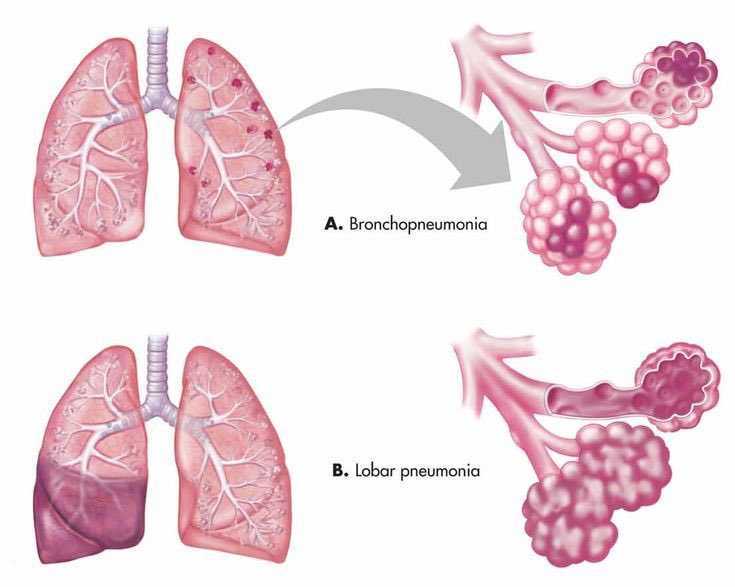

Острая внебольничная пневмония по МКБ-10: признаки и примеры